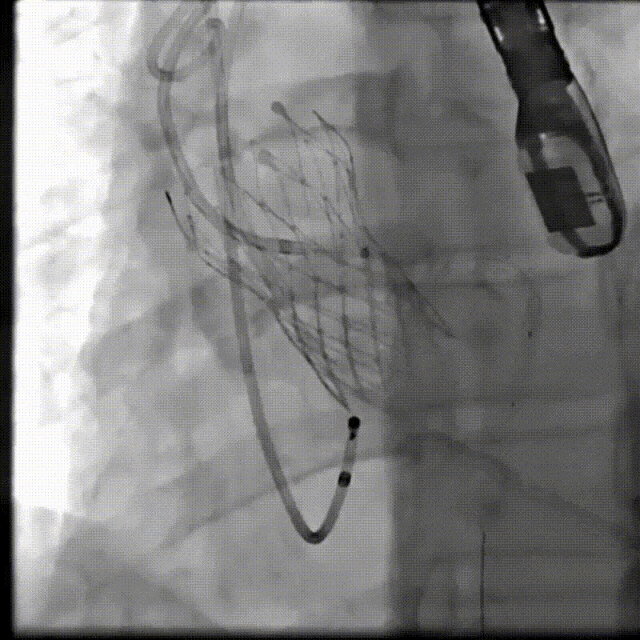

(1)Type 0二叶式主动脉瓣,瓣环适中,中度钙化,Type 0二叶瓣受瓣口形态及钙化影响,瓣架呈非理想椭圆形展开,对瓣架支撑力与顺应性提出了更高要求,同时该病例合并升主扩张,对同轴性和释放的稳定性提出了更高的要求。因此优先选择支撑性和顺应性兼具的瓣膜,以及较柔软花冠的瓣膜,降低对升主动脉的损伤,小锥角的设计进一步提升了瓣膜在释放的稳定性

(2)窦部空间较小,左侧瓣叶冗长,且开口位置在短轴平面,左冠冠脉风险较高,优先选择有收腰设计的瓣膜,降低冠脉风险并保留术后足够的VTC

综合病例解剖特点及患者年纪,决定使用第二代可回收的自膨瓣,可回收提高容错空间,为了降低冠脉阻挡风险,决定采用平衡收腰设计的TaurusElite 的瓣膜,先使用大鞘鞘芯进行预扩,然后上20F大鞘。